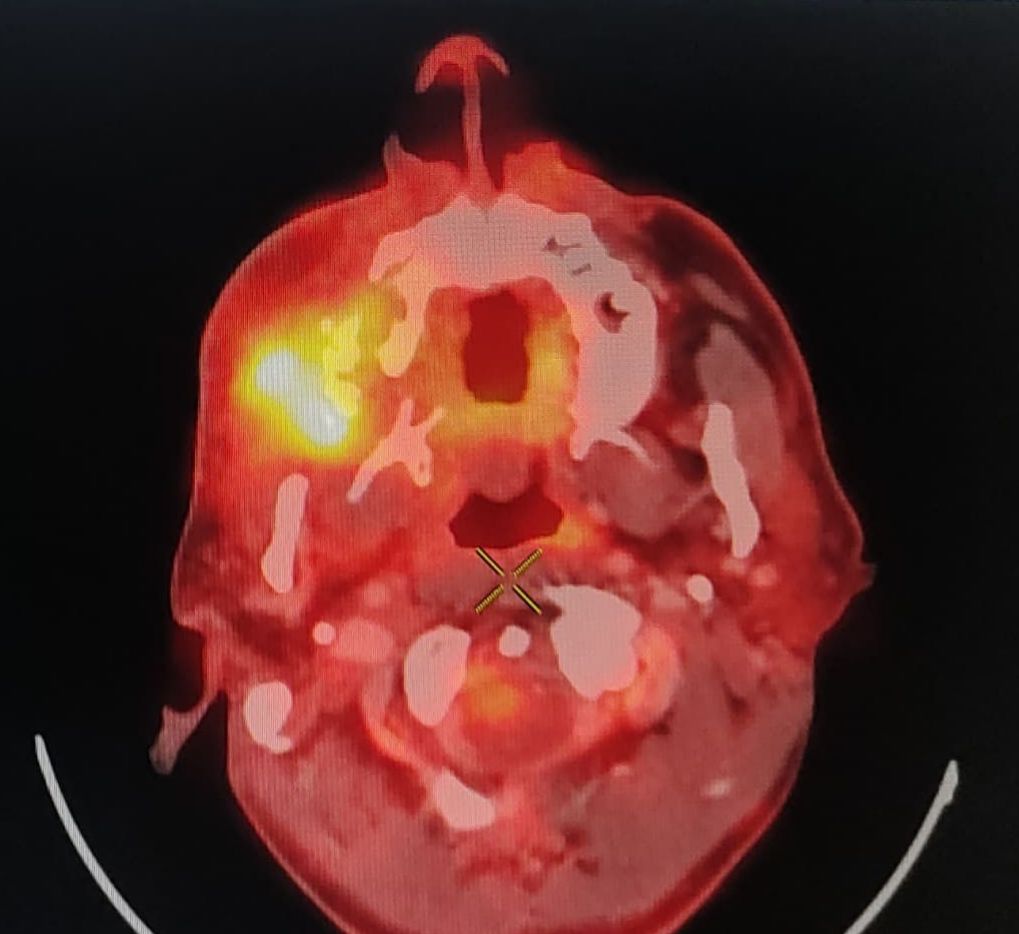

- Intelligent Reporting: Dedicated subspecialty radiologists for every scan, ensuring precise, clinically relevant, and actionable reports.

- Technical Support & Quality Enhancement: We provide active support to imaging centers in improving scan quality through protocol optimization, technical guidance, and training of their on-site technicians as required.